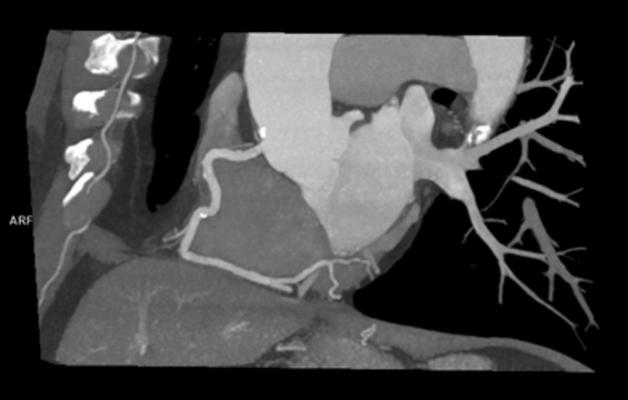

Coronary computed tomography arteriography (CCTA), a kind of CT that gives highly detailed images of the heart vessels, is a promising tool for refining risk assessment — so promising that a multidisciplinary working group recently introduced a scoring system for summarizing CCTA results. The decision-making tool, known as the Coronary Artery Disease Reporting and Data System (CAD-RADS), emphasizes stenoses, or blockages and narrowing in the coronary arteries. While CAD-RADS is an important and useful development in the management of cardiac patients, its focus on stenoses may leave out important information about the arteries, according to study lead author Kevin M. Johnson, M.D., associate professor of radiology and biomedical imaging at the Yale School of Medicine in New Haven, Conn.

Noting that CCTA shows more than just stenoses, Johnson recently investigated a machine learning (ML) system capable of mining the myriad details in these images for a more comprehensive prognostic picture.